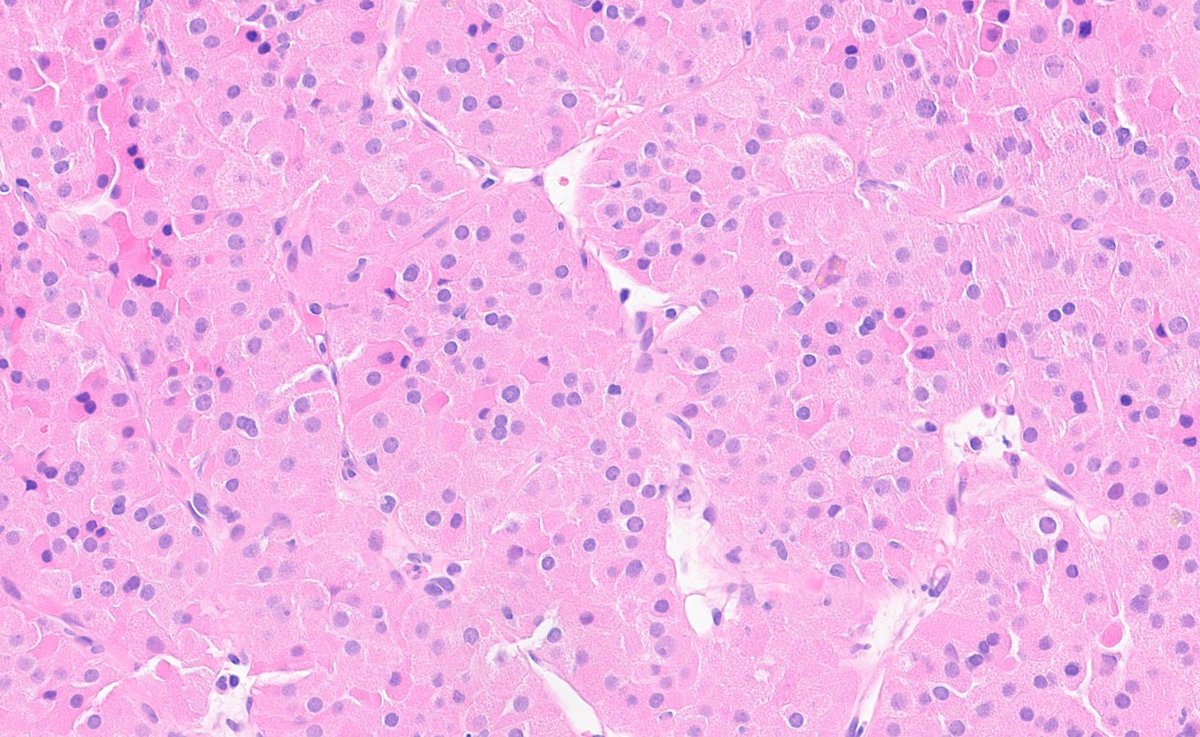

Prostate cancer w/foamy gland features - note the pyknotic nuclei in foamy glands = deceptively benign-appearing Fortunately, as in this example, often admixed with usual acinar #prostatecancer with more amphophilic cytoplasm, prominent nucleoli, etc. #gupath

1

13

38